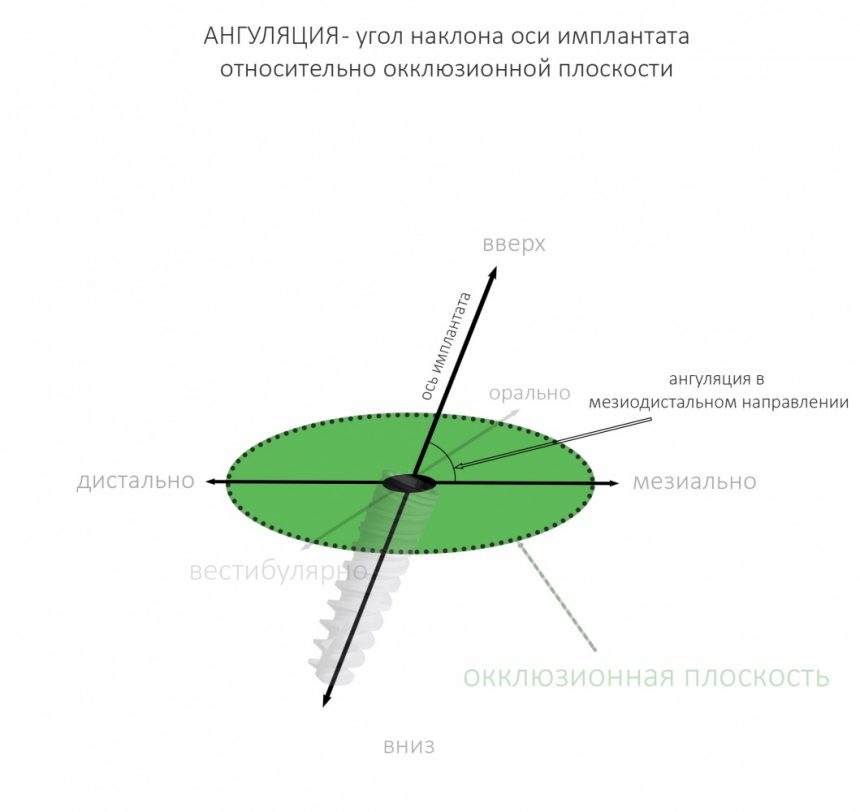

Однако, наш имплантат не сферический в вакууме, а ортопедический интерфейс — не точка. Поэтому, помимо 6 направлений, нужно ввести еще и т. н. «ангуляцию», т. е величину угла между окклюзионной плоскостью и осью имплантата:

Я разделяю ангуляцию на , оптимальную, допустимую и критическую. Разницу между ними поясняет картинка ниже:

Ангуляция — это наш союзник и наш враг. С одной стороны, изменением наклона оси имплантата мы можем исправить изначально неправильное позиционирование по окклюзионной плоскости. С другой стороны, критической ангуляцией можно испортить даже правильно установленный по плоскости имплантат. В общем, хитрая это штука, и рассматривать её мы будем в контексте общего позиционирования.

Гораздо менее понятная штука — это ангуляция имплантата, т. е. угол, образуемый осью импланта и акклюзионной плоскостью альвеолярного гребня.

Если бы челюстная кость имела бы правильную геометрическую форму (например, параллелепипеда), то не было бы нужды рассматривать ангуляцию — мы ставили все наши имплантаты под углом 90 градусов к окклюзионной плоскости, и было бы всем счастье:

Чуть выше я уже говорил, что ангуляция может быть оптимальной, допустимой и критической. Последняя делает протезирование на таком импланте просто невозможным:

Суть в том, чтобы при установке имплантата его ось оставалась в пределах конуса, описываемого допустимой ангуляцией, а в идеале — в пределах описываемого оптимальной: